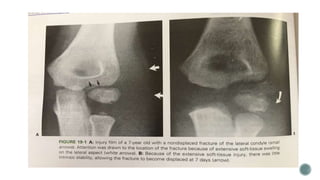

 Fractures involving the lateral condyle in the immature skeleton can either cross the

physis or follow short distance into troclear cartilage

Stages of displacement

 Jakob et al.

First stage – fracture is displaced and the articular surface is intact

 Second stage

Fracture extends completely through the articular surface leading to proximal fragment

to become more displaced and can allow lateral displacement of the olecranon

 Third stage

The condylar fragment is rotated and totally displaced laterally and proximally , allowing

olecranon and radial head translocation